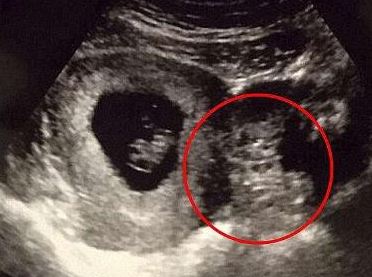

第一次看到宝宝的超音波照片,准父母们一定会很激动。但不久前,国外一名网友带妻子去做检查时,却看到了惊人的一幕。超音波检查照片中显示的不是胎儿的形状,反而看起来像一台跑车。他觉得非常吃惊,将这张照片上传到网路上与大家分享,很快就有490多人留言回应。

这张超声波照片看起来很像跑车,就连车窗、车轮都看得很清楚。

网友们纷纷表示,「这绝对会引发中年危机」

还有人说「不要忘了踩煞车」。